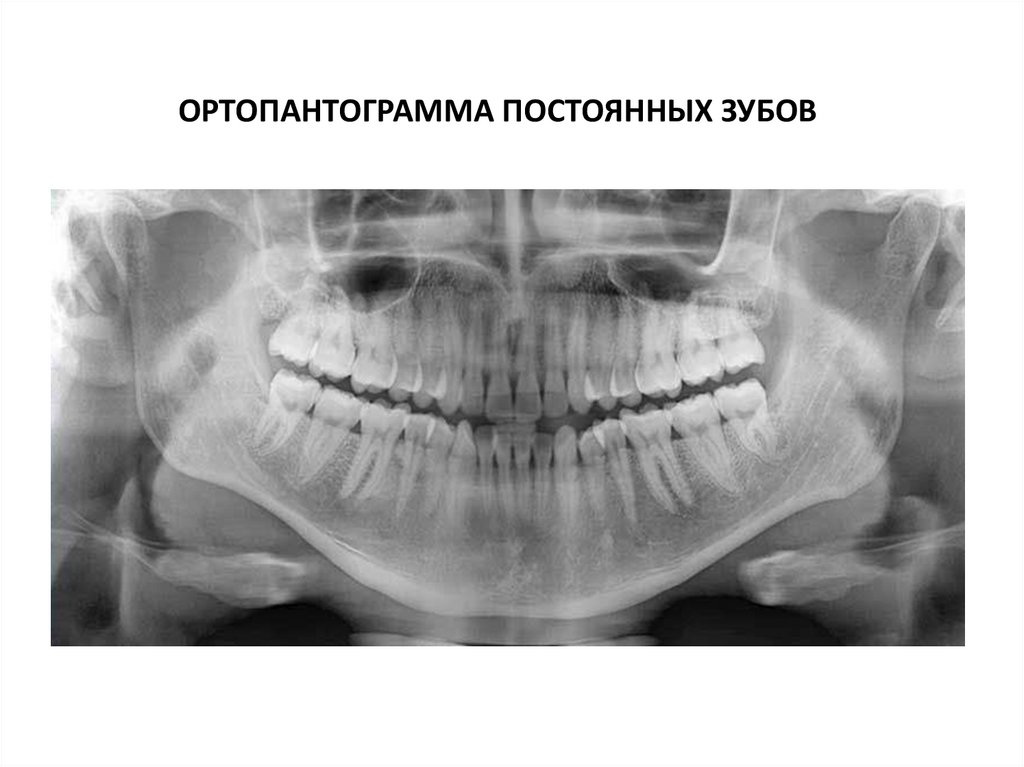

Ортопантограмма постоянных зубов.

Третьи нижние моляры не прорезались.

Третьи верхние моляры прорезались не полностью

ОРТОПАНТОГРАММА ПОСТОЯННЫХ ЗУБОВ

Ортопантограмма

1.головка нижней челюсти

2.нижнечелюстная ямка

височной кости

3.костное небо

4.верхнечелюстная пазуха

5.носовая вырезка

6.щечно-дистальный корень

первого верхнего моляра

(левого)

7.канал нижней челюсти

8.ветвь нижней челюсти

9.угол нижней челюсти

10. Основание нижней

челюсти

11.венечный отросток

нижней челюсти

12.Медиальный верхний

резец (левый)

13.подъязычная кость

14.сосцевидный отросток